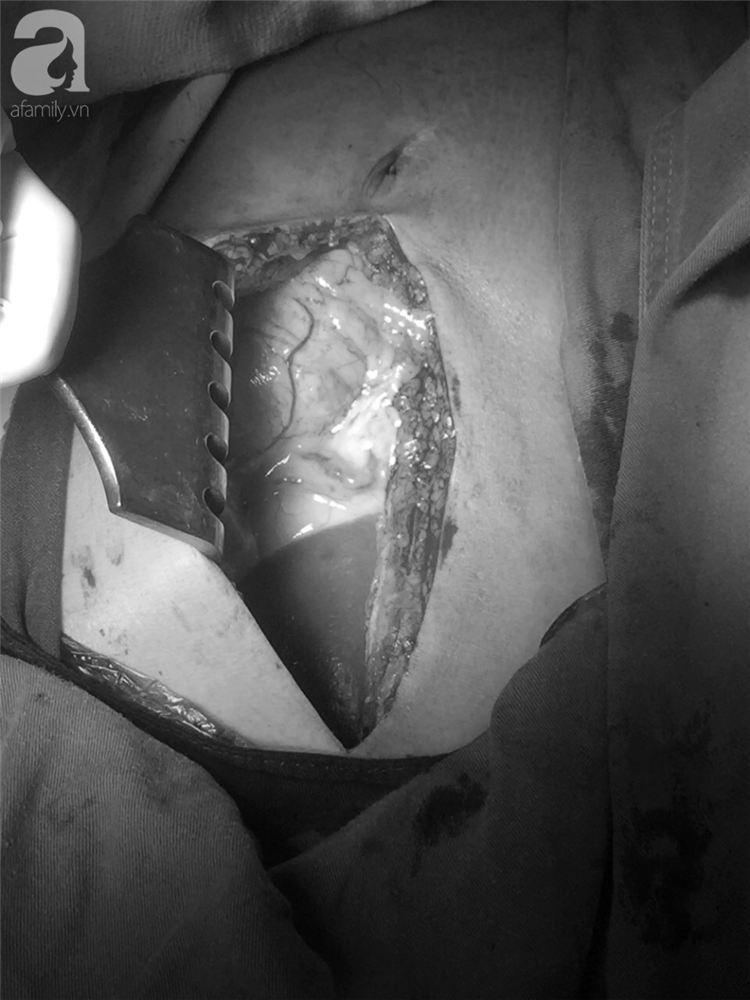

Ca phẫu thuật kéo dài trong 105 phút cứu sống bệnh nhân.

20 phút sau, các bác sĩ ở BV Bình Dân đã có mặt. Ekip phẫu thuật của hai BV đã phối hợp khâu lại vết rách ở thành tâm thất trái, khâu vết rách ở thùy trên phổi phải, vết rách cơ hoành, dẫn lưu kín khoang màng phổi…Sau 105 phút, ca phẫu thuật hoàn thành.